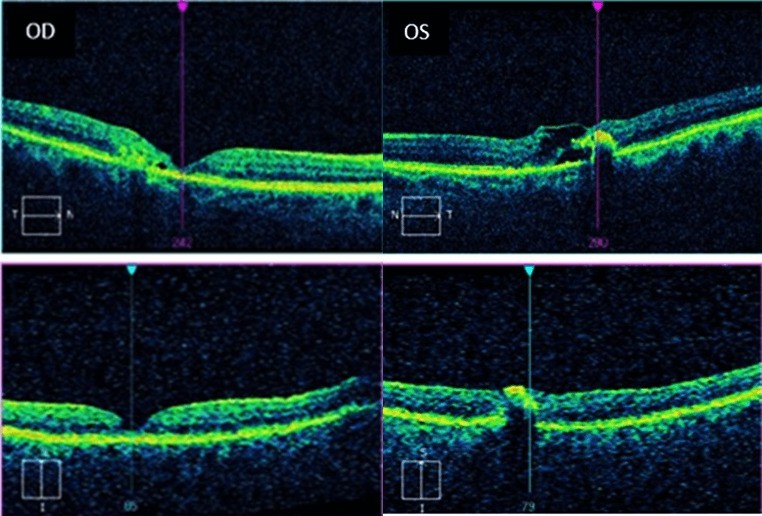

Figure 2. OCT of the right eye revealed central atrophy and trace subretinal cystic changes. OCT of the left eye appeared to have extensive intraretinal and subretinal cystic changes centrally, internal limiting membrane draping, and a pigment epithelial detachment temporal to the fovea.

OCT aids in the diagnosis and is an essential part of monitoring MacTel type 2. Intraretinal cysts along the inner retina near the foveola are classic findings of MacTel type 2 on OCT scans. These cysts are not a result of leakage or exudation but rather represent tissue degradation and loss.1 As a result, a common finding characteristic to MacTel type 2 is internal limiting membrane (ILM) draping.11 This is where the thin ILM extends or “drapes” over the top of the intraretinal cyst.11 As the disease gradually progresses, these intraretinal cysts can enlarge and be seen in the outer retina as well.10 RPE hyperplasia may present over time and is seen as hyperreflective plaques that cast a shadow zone beneath them.15 In advanced cases where there is significant visual impairment, foveola atrophy and photoreceptor degradation is apparent.